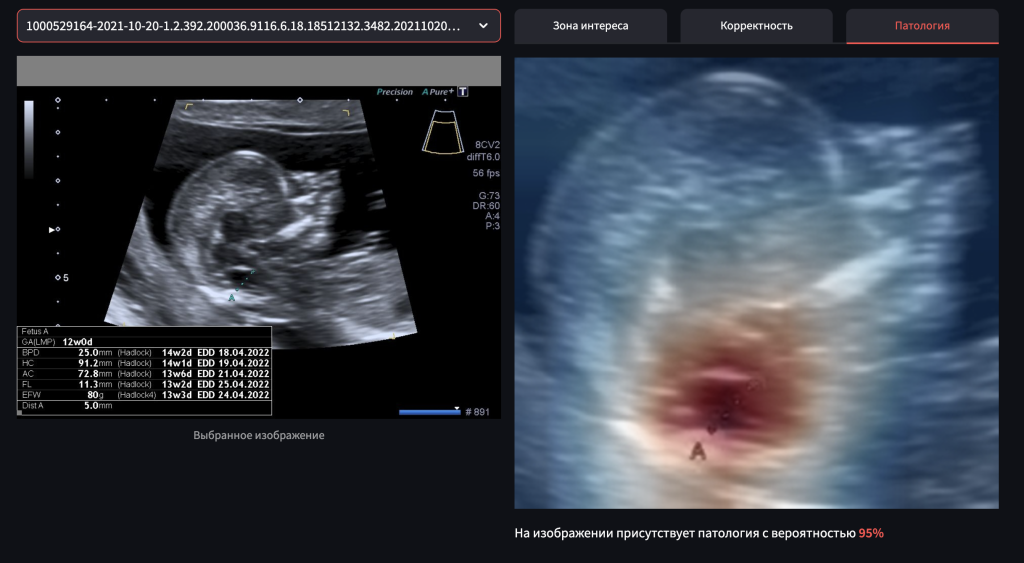

Российская компания «Яндекс» создала ИТ-решение на базе машинного обучения, которое позволяет обнаружить при УЗИ-исследовании беременных женщин симптомы spina bifida у плода. Это тяжелое врожденное заболевание центральной нервной системы, которое встречается у одного из тысячи новорожденных. Решение доступно бесплатно всем врачам и медицинским экспертам на сайте фонда «Спина бифида», который и инициировал данный проект в России. С помощью технологии медицинские специалисты смогут увидеть признаки spina bifida еще до рождения ребенка и направить пациентку на дополнительное обследование. Для этого врач должен предоставить нейросети результаты УЗИ, сделанные во время первого скрининга. Программа автоматически проанализирует снимок и определит вероятность spina bifida. Для машинного обучения использован уникальный датасет из порядка шести тысяч обезличенных изображений УЗИ беременных женщин, собранный специалистами НМИЦ акушерства, гинекологии и перинатологии имени академика В. И. Кулакова

С помощью технологии медицинские специалисты смогут увидеть признаки spina bifida еще до рождения ребенка и направить пациентку на дополнительное обследование. Для этого врач должен предоставить нейросети результаты УЗИ, сделанные во время первого скрининга. Программа автоматически проанализирует снимок и определит вероятность spina bifida. Для машинного обучения использован уникальный датасет из порядка шести тысяч обезличенных изображений УЗИ беременных женщин, собранный специалистами НМИЦ акушерства, гинекологии и перинатологии имени академика В. И. Кулакова.